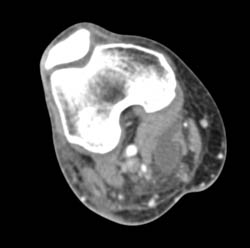

Diagnosis

Myeloma